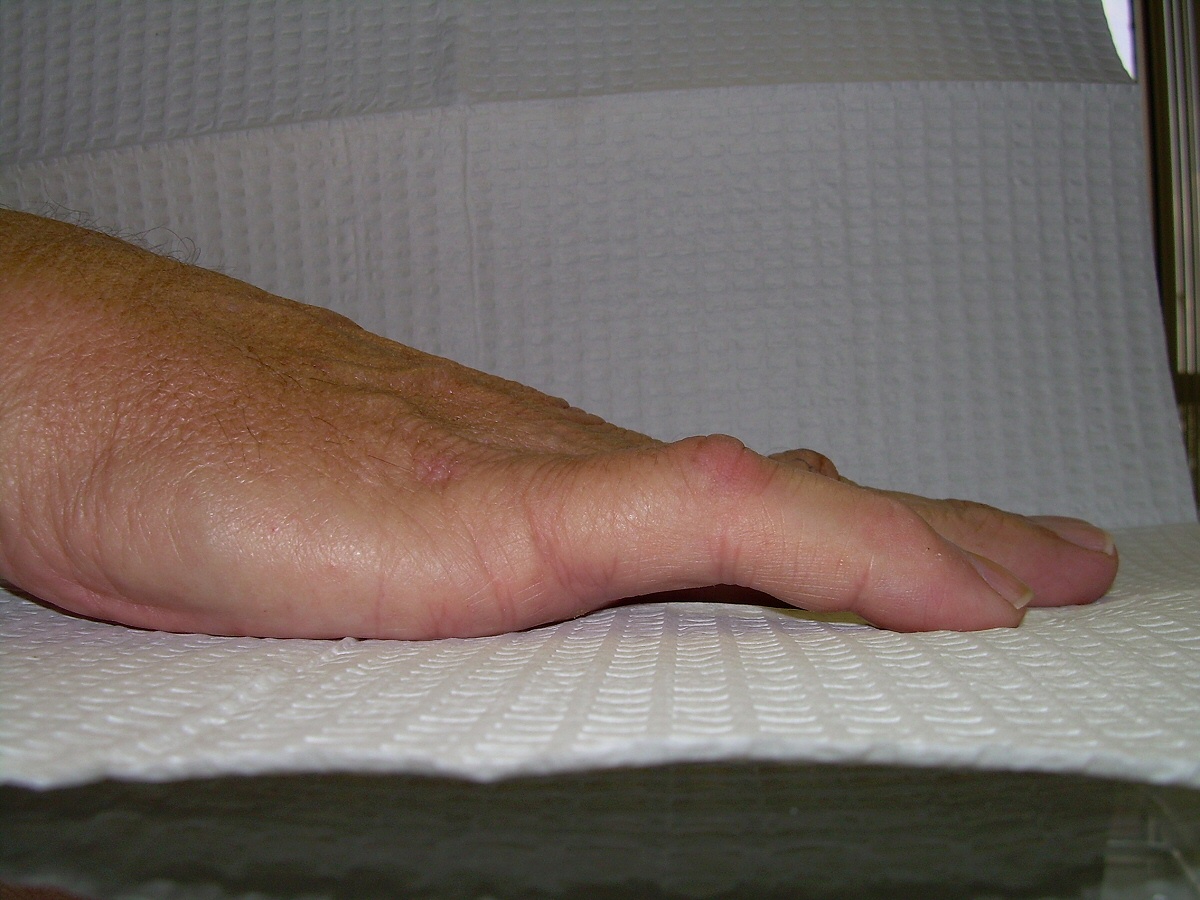

Case 4.

57 year old right handed man with a 22 year

history of Dupuytren disease affecting his

left small finger.

Highslide Highslide

Planning of portals (dots) and nodule steroid

injection sites (circles).

Radiograph of affected finger, 90° contracture.